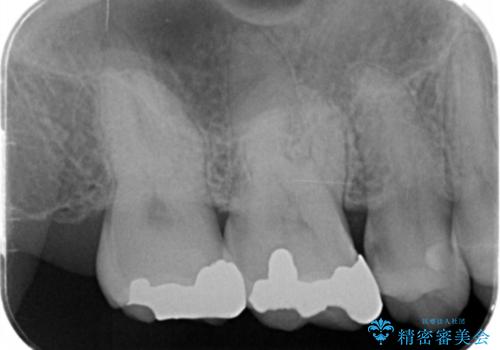

- 口の中に見える銀歯を、金属アレルギーの対策と審美性の向上のため全て除去したい!と希望され来院されました。

銀歯を丁寧に除去したのち、精度の良いセラミックインレー、セラミッククラウンで修復・補綴処置を行っていきます。

- 62.7万円(ジルコニアクラウン×3・仮歯×3・セラミックインレー×3)費用は治療当時の料金となります